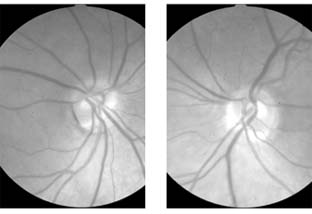

Figure 14-8

Figure 14-8: Mild disk swelling in demyelinative papillitis, with disk leakage on fluorescein angiography.

Papillitis needs to be differentiated from pap-illedema (Figure 14-9). In papilledema there is often greater elevation of the optic nerve head, nearly normal visual acuity, normal pupillary response to light, associated intracranial pressure, and an intact visual field except for an enlarged blind spot. If there has been acute papilledema with vascular decompensation (ie, hemorrhages and cotton-wool spots) or chronic papilledema with secondary ischemia of the optic nerve, visual field defects can include nasal nerve fiber bundle defects and nasal quadrantanopias. Papilledema is usually bilateral, whereas papillitis is usually unilateral. Despite these obvious differences, differential diagnosis can be difficult because of the similarity of the ophthalmoscopic findings and because papilledema can be quite asymmetric and papillitis bilateral in some postviral events (eg, Devic's disease, or neuromyelitis optica; see below).

Figure 14-9

Figure 14-9: Mild papilledema. The disk margins are blurred superiorly and inferiorly by the thickened layer of nerve fibers entering the disk.